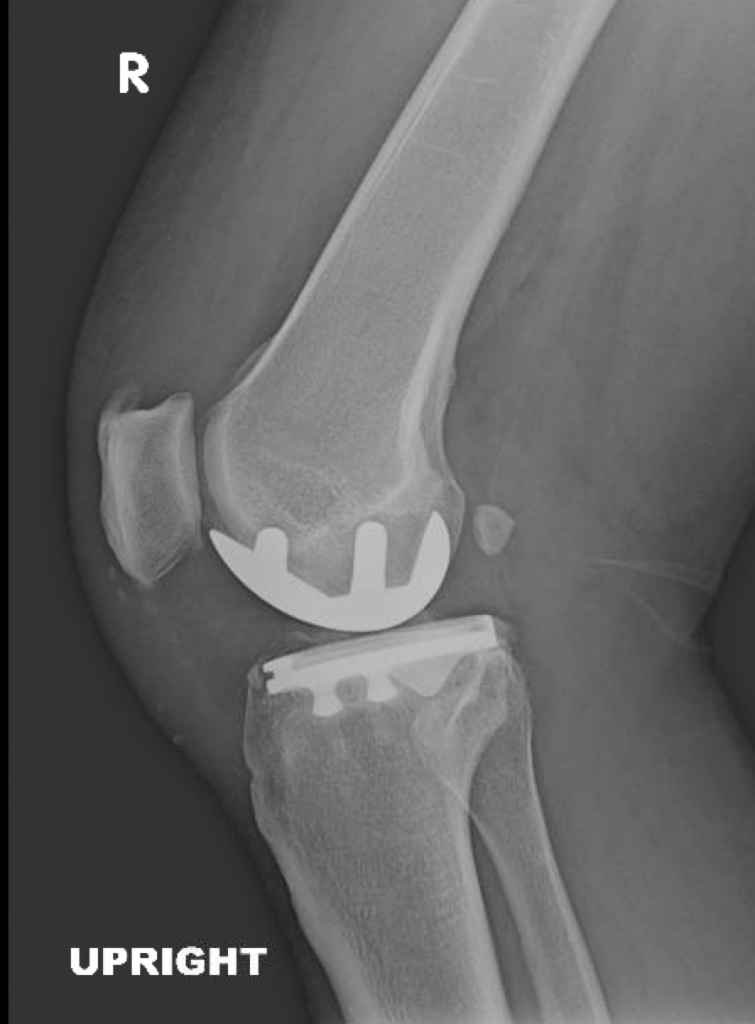

This is a 67 year old male with isolated medial compartment arthritis of the right knee. His lateral and patellofemoral compartments were pristine and his symptoms consisted of 100% medial sided pain.

He underwent minimally invasive, outpatient partial knee replacement and walked home the same day with a cane.